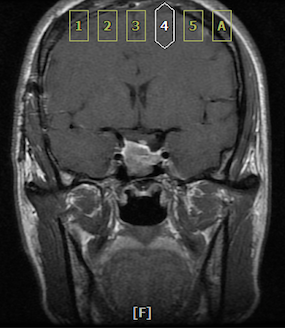

头颅MRI示肿瘤主体位于鞍内,质地硬韧,与颈内动脉粘连紧密

垂体动态增强示右侧鞍上池受压上抬,鞍隔显示不清,肿瘤不均质增强